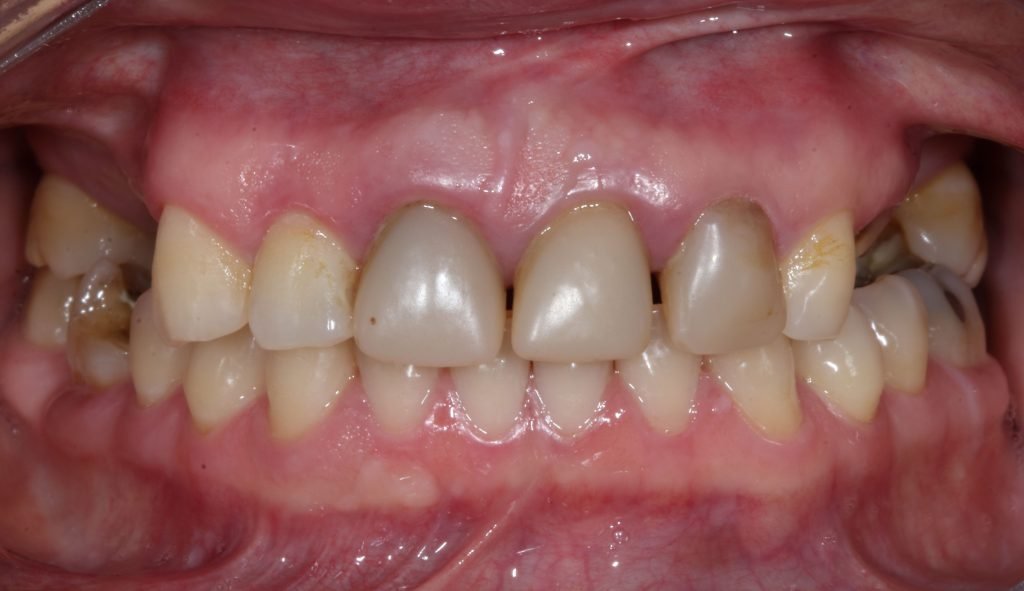

Punto Bajío Casos Clínicos Prótesis Fija sobre Implante unitario Inicio Provisional Final Prótesis Parcial Fija sobre 2 Implantes 2 Implantes Final Prótesis Bucal Removible Inicial Inicial Superior Inicial Inferior Rayos X Inicial Rayos X Inicial Frontal Final Final Superior Final Inferior Prótesis Parcial Fija/ Coronas de Circonio Sonrisa Inicial Foto Inicial Foto Inicial Inferior Foto Final Inferior Foto Final Sonrisa Final Prótesis Total Protesis Inmediatas 1 Protesis Inmediatas 2 Prótesis Removible/ Coronas Metal-Ceramica Carillas Incrustaciones Endodoncia